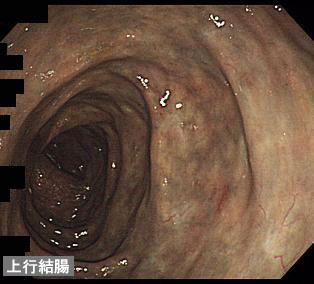

症例提示(所在地,施設名等): 福岡県・ 九州医療センター (放射線科、宮田景子先生、平賀聖久先生、村中光先生からの提供症例)

症例登録日 2010/12/25

画像数 22

性別 男性

年齢 60-64

画像ID:11550

疾患(病理主体)の分類炎症性・潰瘍性疾患/静脈硬化性大腸炎

部位(臓器別)大腸/2区域以上の大腸にまたがるもの

検査方法内視鏡